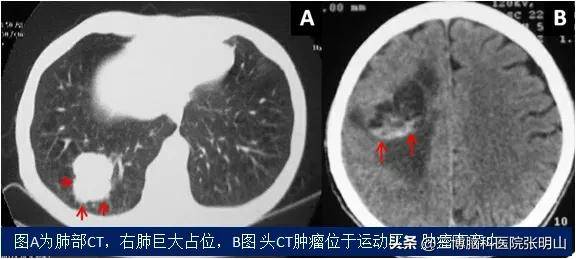

脑转移瘤是指原发于身体其他部位的肿瘤细胞如肺癌细胞、乳腺癌细胞、胃癌细胞等转移至颅内,从而造成颅内肿瘤生长的一种疾病。表现主要有头痛、呕吐、视物模糊、偏瘫、语言不清等。患者往往有其他部位肿瘤病史。

影像学检查主要包括增强CT及磁共振成像(MRI)。根据原发肿瘤类型及患者的病情选择不同治疗措施,通常选择手术加放疗、化疗等综合治疗措施。